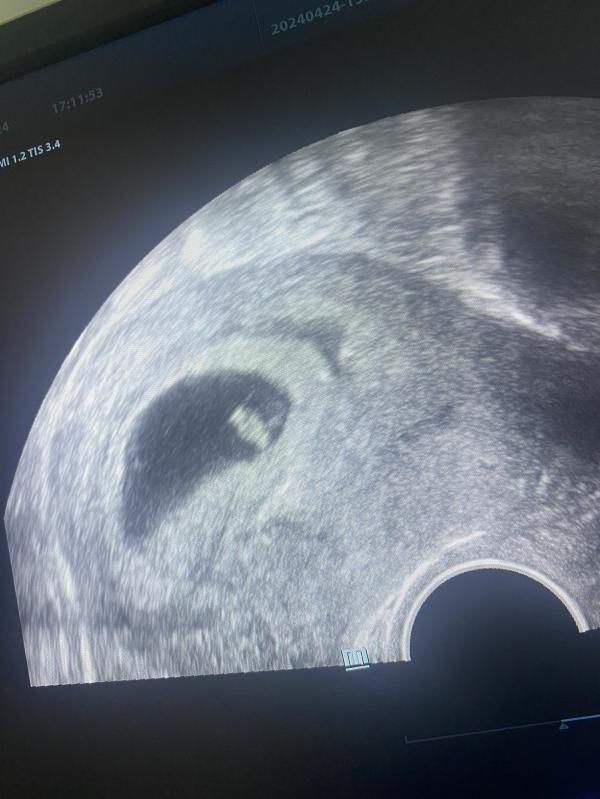

7 недель 5 дней: услышала сердечко креветочки! Это любовь?

Моя маленькая креветочка🥹❤️моя бесконечная любовь 🤲🏼❤️

Я услышала твое сердечко и это самое волшебное,чтоб могло произойти 🤲🏼

Срок по узи 7 недель и 5 дней🤲🏼🥹